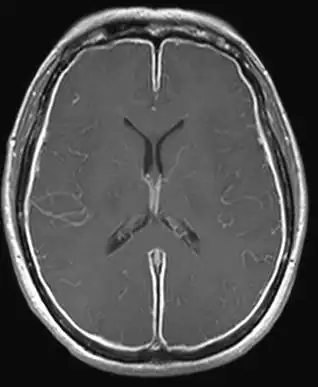

| Ressonância magnética de cérebro com meningite bacteriana asséptica | |